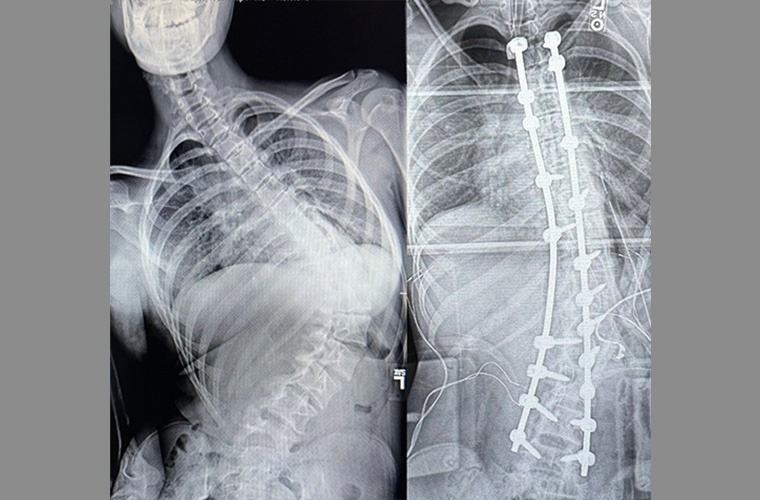

Within 18 months post-surgery, the curvature had escalated from 55 degrees to a dramatic 98-degree bend. Her spine became C-shaped putting pressure on her internal organs and causing pain. If not corrected, it could result in breathing difficulty and other complications.

Over the course of the 8-hour surgery, Dr. Siambanes and his surgical team successfully inserted a metal rod to fuse Madison Lockert’s spine and correct her posture. The result has been life changing, particularly considering her other challenges, explained her mother.